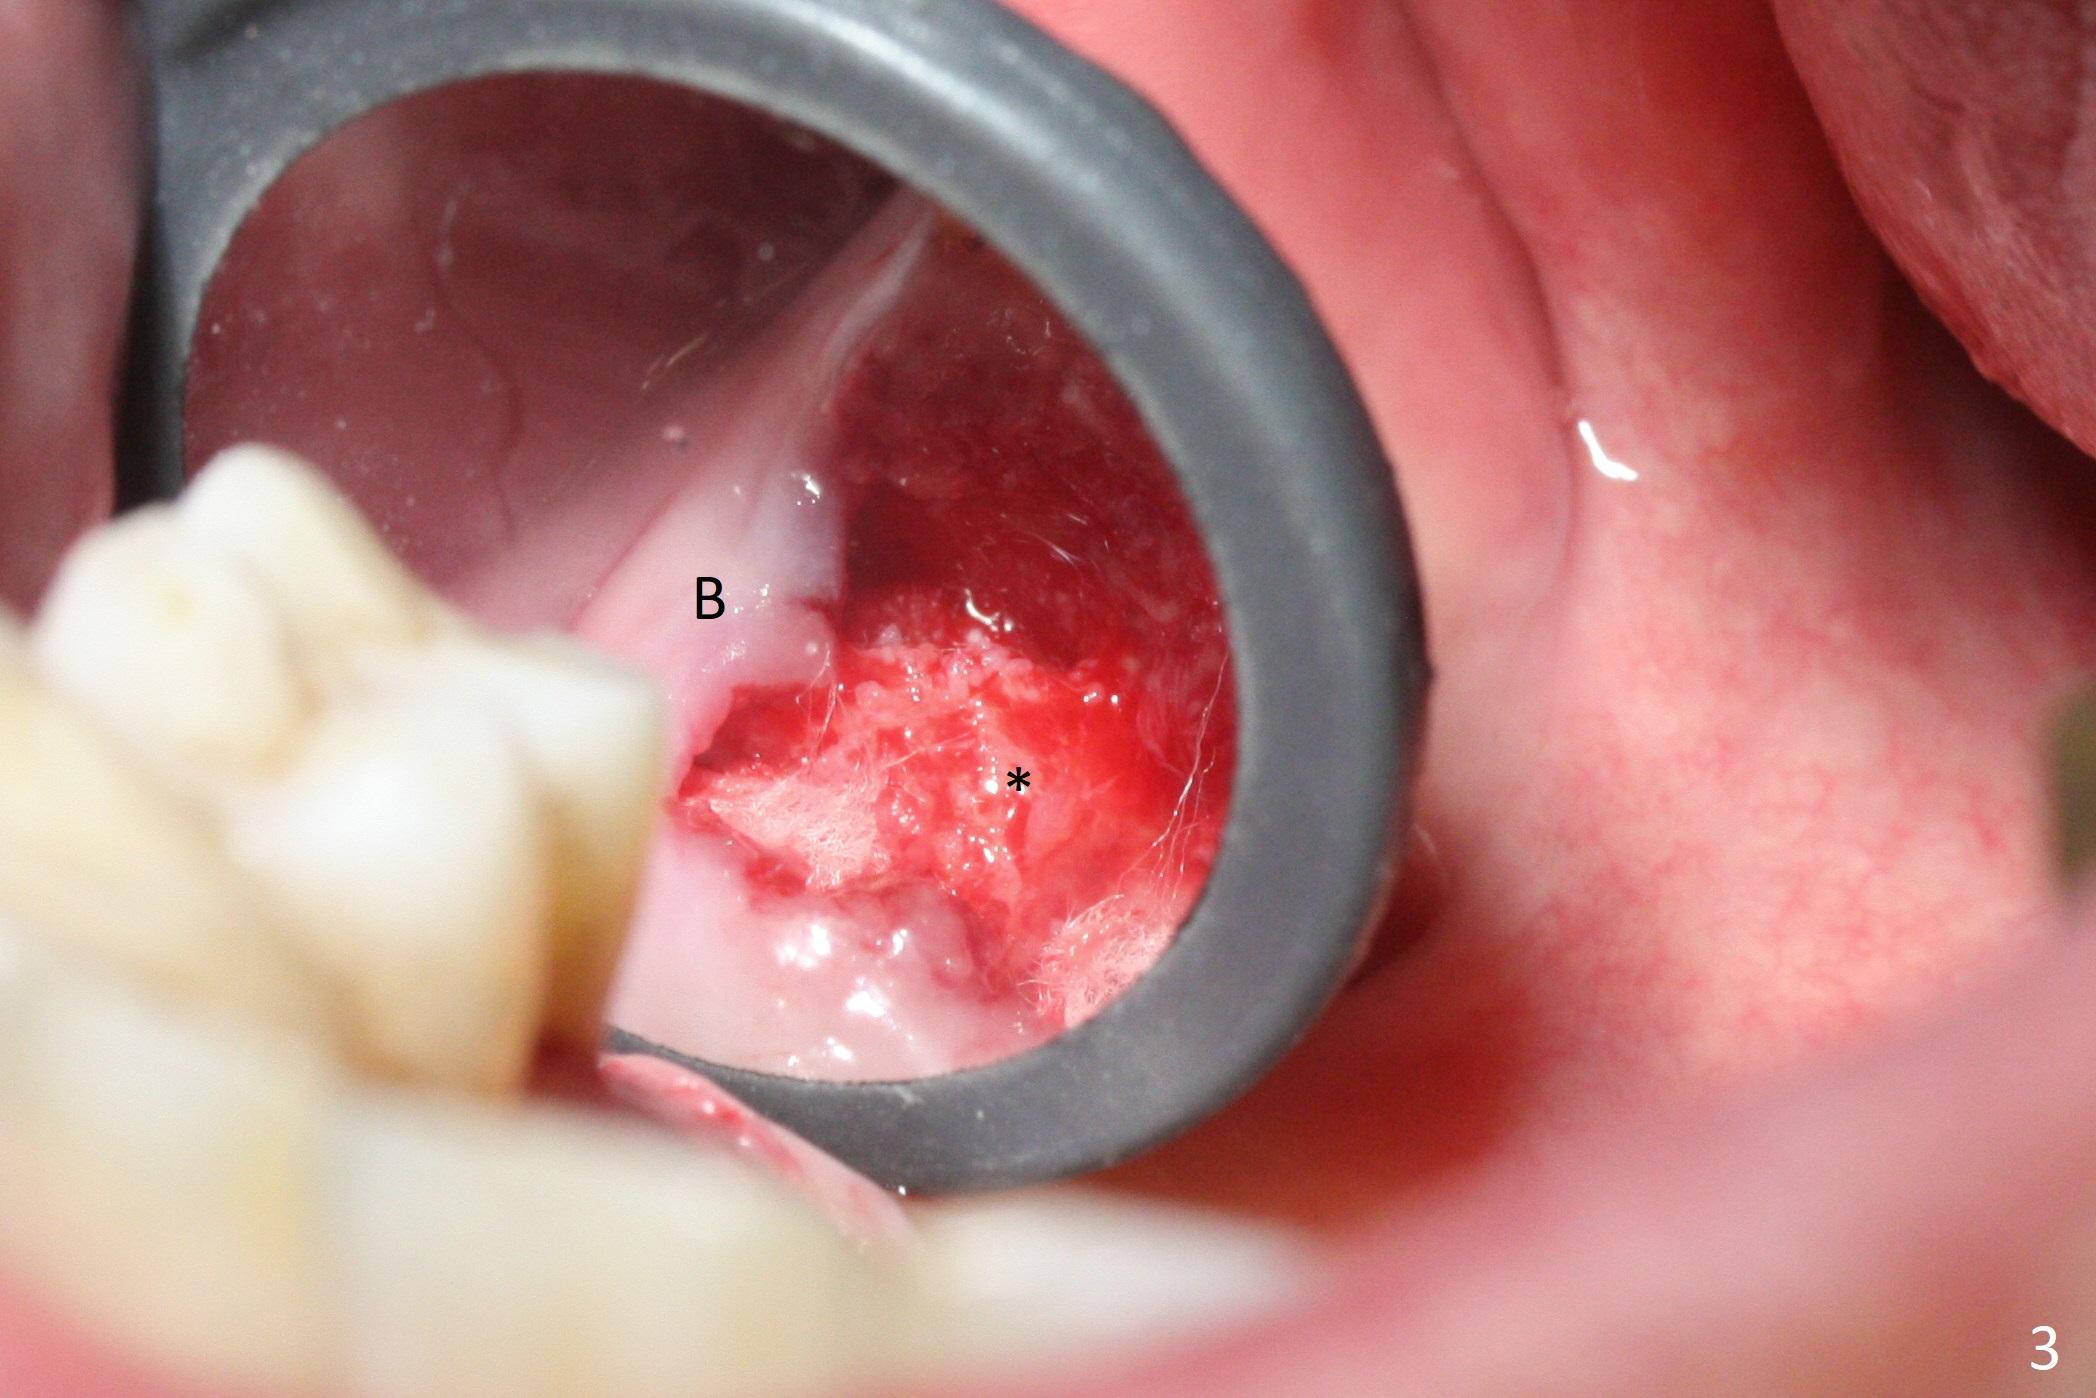

Buccal gingival recession at #14 (Fig.1) is less severe than the palatal one (Fig.2). Without raising the buccal gingiva (Fig.3 B), osteotomy in the septum is established apparently in the middle socket (Fig.3 *, 4). As the osteotomy increases with 3.8 mm drill, the palatal wall of the osteotomy starts to be perforating. When a 4.5x11.5 mm implant is placed, palatal threads are exposed, to which autogenous bone and Vera Graft are placed (Fig.5 *). After placement of a 5.5x5(3) mm abutment, an immediate provisional (Fig.6 P) is fabricated to cover the sockets. If the septal dimension were studied carefully by raising the buccal gingiva slightly, the osteotomy could be initially more buccal so that the palatal thread exposure could be less. When the provisional is removed 1.5 months postop, the implant is exposed palatally. The margin of the provisional is modified so that the implant can be cleaned by the patient using Water Pik. In fact, the healthy gingiva seems to be attached to the implant threads 2 weeks later (Fig.7). The distal implant threads remains exposed 6 months postop; it appears that the distal socket wall has resorbed (Fig.8). The sockets heal 1 year 7 months post cementation (Fig.9).